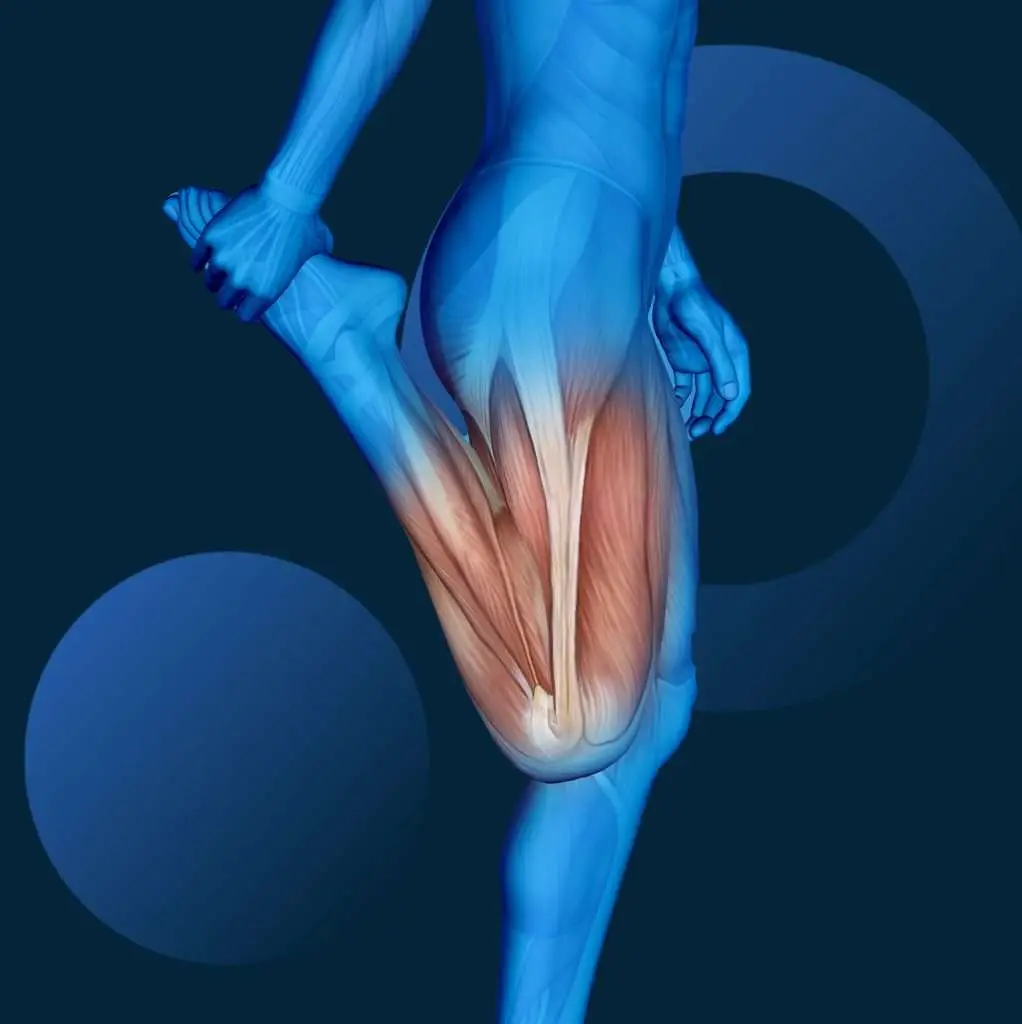

Für den Patienten beginnt die Wahrheit jedoch erst beim ersten Schritt. Und hier zeigt die biomechanische Forschung eine brutale Realität: Nicht das Titan entscheidet darüber, wie schnell der Patient die Treppe steigt, sondern der M. quadriceps femoris.

- Massive Atrophie: Studien zeigen, dass Coxarthrose-Patienten auf der betroffenen Seite präoperativ bereits 10–20 % weniger Muskelmasse im Oberschenkel haben als auf der gesunden Seite.

Wir operieren also in ein funktionelles Defizit hinein. Wir bauen ein High-End-Gelenk in ein muskuläres System ein, das buchstäblich „auf dem Zahnfleisch geht“. Das Resultat: Das Gelenk ist beweglich, aber dem Patienten fehlt die Kraft (Motor), es zu stabilisieren. Das führt zu Gangunsicherheiten, Stürzen und der gefürchteten postoperativen Unzufriedenheit („Es tut immer noch weh“).

Die Datenlage ist eindeutig: Die präoperative Quadriceps-Stärke ist einer der validesten Prädiktoren für das postoperative funktionelle Ergebnis (insb. bei Knie-TEP, aber auch Hüfte).

- M. quadriceps femoris: Für die Standphase und das Aufstehen.